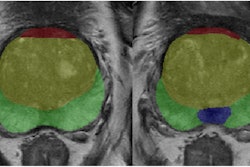

Elucirem (gadopiclenol) has been approved by the European Commission for use in adults and in children from birth for contrast-enhanced MRI to improve detection and visualization of pathologies with disruption of the blood-brain barrier and/or abnormal vascularity of the brain, spine, and associated tissues of the central nervous system as well as the liver, kidney, pancreas, breast, lung, prostate, and musculoskeletal system.

The firm added that Elucirem requires half the conventional gadolinium dose as existing nonspecific contrast agents, thus reducing gadolinium exposure for patients.